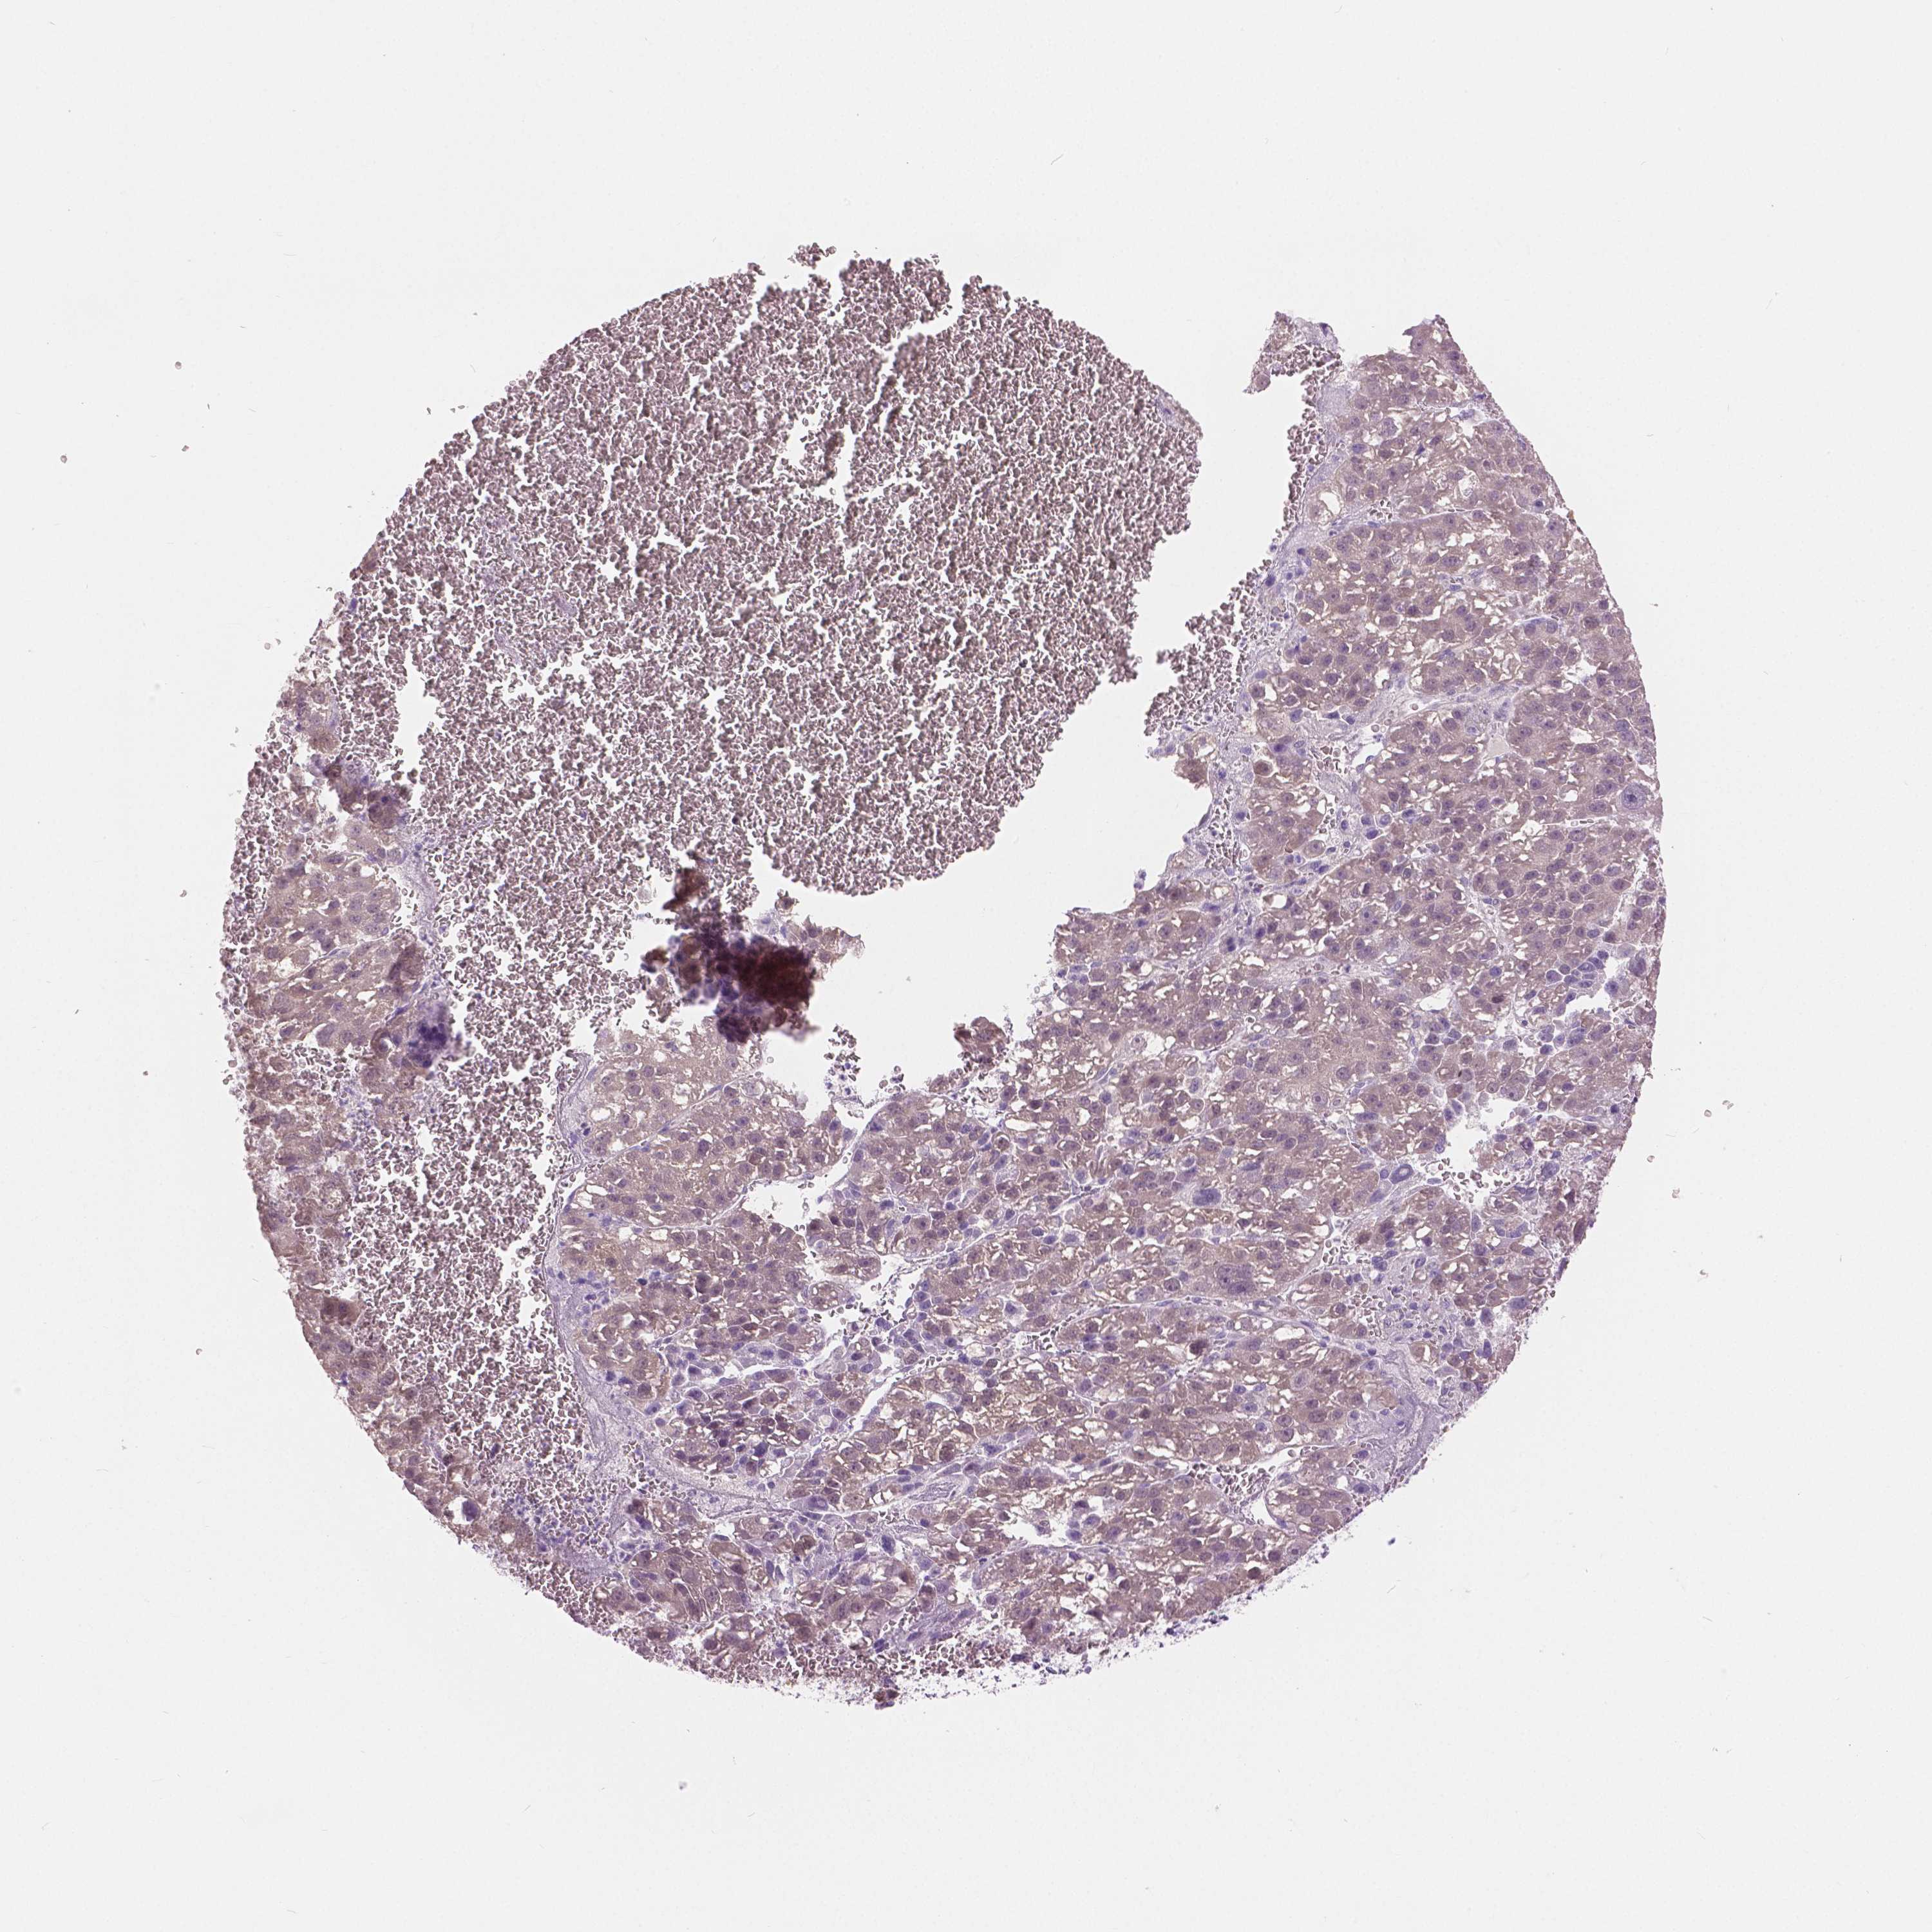

LIVER CANCER - Protein expressioni

A mouse-over function shows sample information and annotation data. Click on an image to view it in a full screen mode. Samples can be filtered based on level of antibody staining by selecting one or several of the following categories: high, medium, low and not detected. The assay and annotation is described here.

Note that samples used for immunohistochemistry by the Human Protein Atlas do not correspond to samples in the TCGA dataset.

Antibody stainingi

Antibody staining in the annotated cell types in the current human tissue is reported as not detected, low, medium, or high, based on conventional immunohistochemistry profiling in selected tissues. This score is based on the combination of the staining intensity and fraction of stained cells.

Each image is clickable and will lead to virtual microscopy that enables deeper exploration of all samples and also displays staining intensity scores, fraction scores and subcellular localization as well as patient and tissue information for each sample.

Antibody HPA035472

Antibody HPA035473

Antibody HPA064835

Staining

Carcinoma, Hepatocellular, NOS

Cholangiocarcinoma